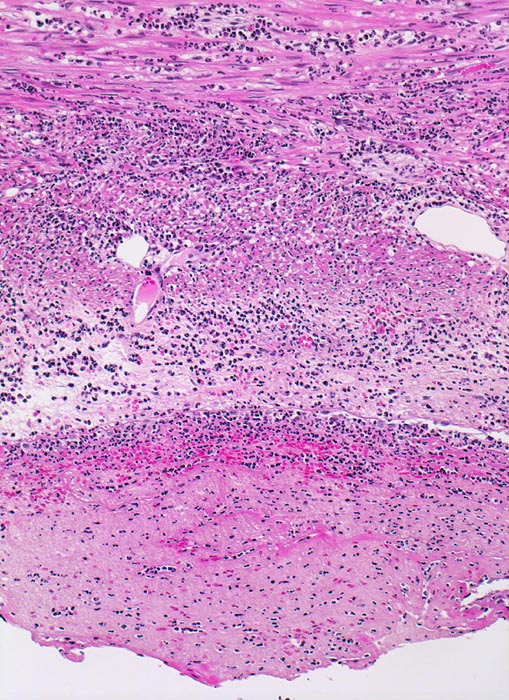

PathoPic – image database / PathoPic ID 3433 - akute Appendizitis: fibrinös eitrige Peritonitis

akute Appendizitis: fibrinös eitrige Peritonitis

Das Peritoneum unten im Bild wird bedeckt von einer dicken Schicht bestehend aus neutrophilen Granulozyten und Fibrin. Die Muscularis propria der Appendix zeigt ein phlegmonöses Entzündungsinfiltrat.